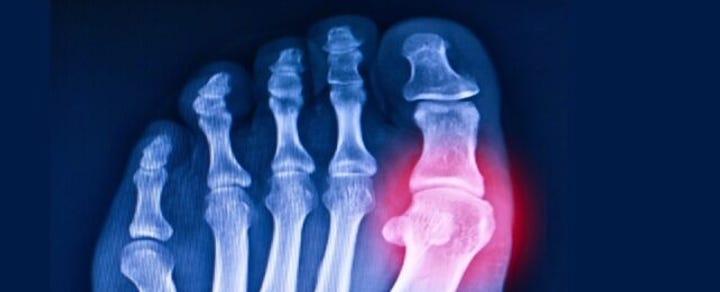

Cercetătorii de la Universitatea de Stat din Georgia reînvie o genă veche de 20 de milioane de ani folosind editarea genetică CRISPR cu scopul de a combate guta și alte afecțiuni legate de acidul uric...pescurt.ro Sep 05, 2025